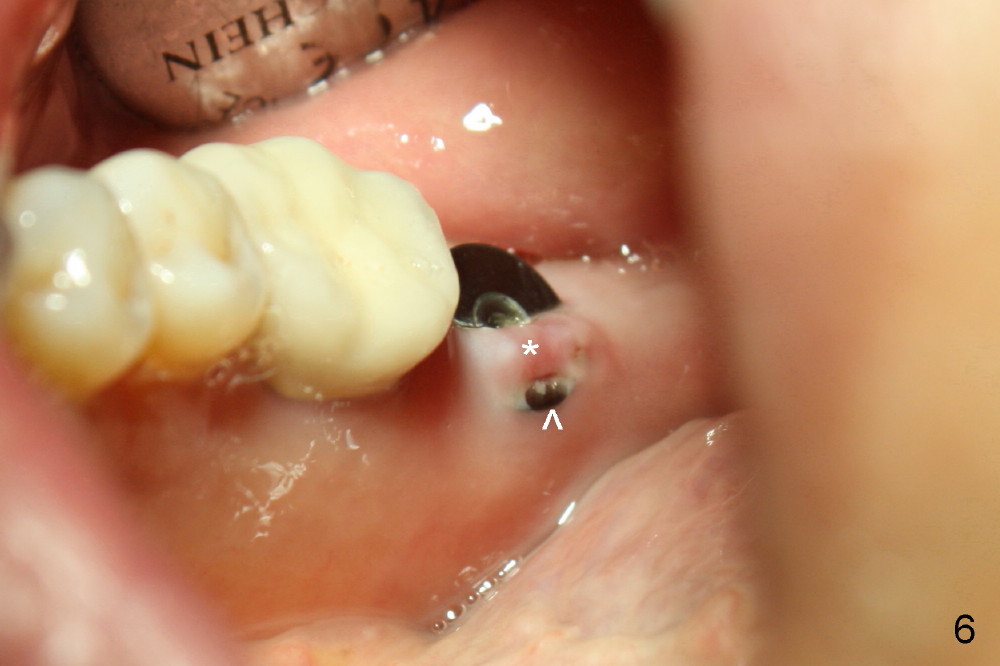

No. First at all, CT should be taken when 2D image does not show IAN. Fortunately, the surgery happens to be executed better than the plan. Clindamycin is used for socket soaking for 5 minutes. The initial osteotomy should be not exceeded 6 mm from the distal surface of the first molar (Fig.3: 5.92 mm). The 2 mm pilot drill (D) penetrates the mesial slope of the socket (red line) for 3-4 mm. There is 2.72 mm from IAN (yellow line: upper border of IAN canal). If the implant is placed along the long axis of the tooth, the initial osteotomy should start at the apex of the socket. The same pilot drill (black outline) penetrates the nascent bone for the same distance (3-4 mm) for primary stability, IAN may be invaded! The patient is a severe gagger. She manages to allow us to take this PA (Fig.3) and the next one (Fig.4 with 6x14 mm tap in place, primary stability having been achieved). To close the socket, a 7x14 mm implant is placed. Immediately postop PA is taken twice without success. The socket is closed with 2 sutures and heals around the implant 8 days postop (Fig.5,6). PA is taken 2 months postop (Fig.7). The implant is not placed as deep as planned. It is stable without paresthesia of the lower lip. An abutment is placed (Fig.8: A) nearly 3.5 months postop.